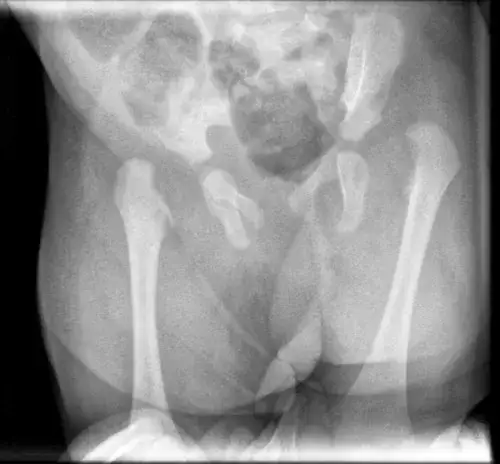

- RTG (zdjęcie rentgenowskie): Jest to podstawowe badanie, które pozwala przede wszystkim wykluczyć złamania kości oraz zwichnięcie stawu. Czasem może uwidocznić pewne zmiany pourazowe w obrębie kostnym.